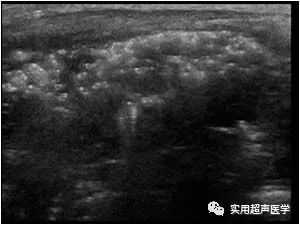

患儿女,6天,新生儿坏死性小肠结肠炎,超声表现为肠壁积气、门静脉及其分支积气、肠管扩张、肠壁血管化。

患儿男,14天,新生儿坏死性小肠结肠炎,肠壁积气、门静脉及其分支积气、腹腔积液。